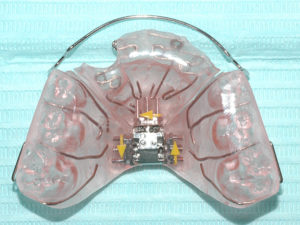

Removable Maxillary Expansion appliances. These appliances have precisely this purpose: To expand the upper dental arch and the maxilla (upper jaw). These appliances can be removable, i.e. patients can place them in and remove them from their mouth depending on the circumstances.

- ΚΙΝΗΤΗ ΣΥΣΚΕΥΗ ΔΙΕΥΡΥΝΣΗΣ

- ΚΙΝΗΤΗ ΣΥΣΚΕΥΗ ΔΙΕΥΡΥΝΣΗΣ

- ΚΙΝΗΤΗ ΣΥΣΚΕΥΗ ΔΙΕΥΡΥΝΣΗΣ

- ΚΙΝΗΤΗ ΣΥΣΚΕΥΗ ΔΙΕΥΡΥΝΣΗΣ

Their advantage is that patients can take them out in order to enjoy they food and – most importantly – to maintain a high level of oral hygiene. The greatest issue is that, usually, their fit inside the mouth is not perfect and/or patients often take them out too often, so the desired treatment outcome is not fully achieved. Personally, I very seldom choose to use such appliances in my practice.